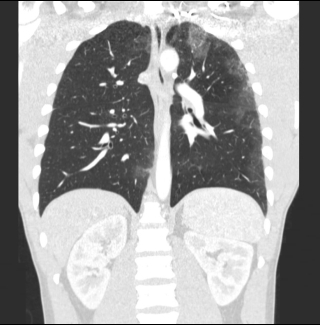

The result - as far as his lungs went - is shown below.

Coughing blood during steroids cycle

The doctors asked the bodybuilder to stop and the symptoms disappeared spontaneously. A few months later the scans showed that the lungs were functioning normally again.